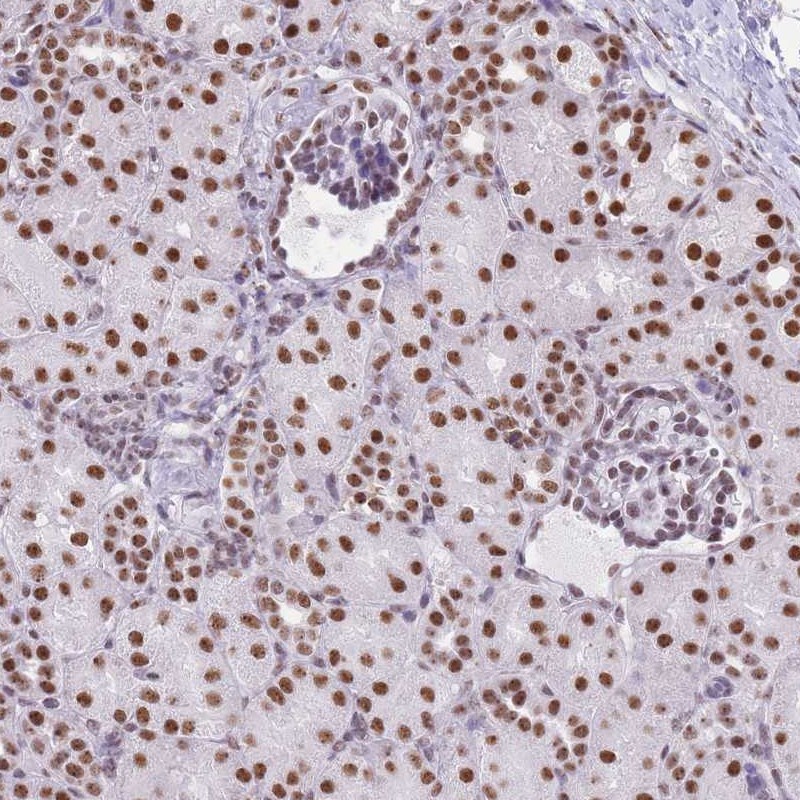

Immunohistochemical staining of human kidney shows strong nuclear positivity in cells in tubules.